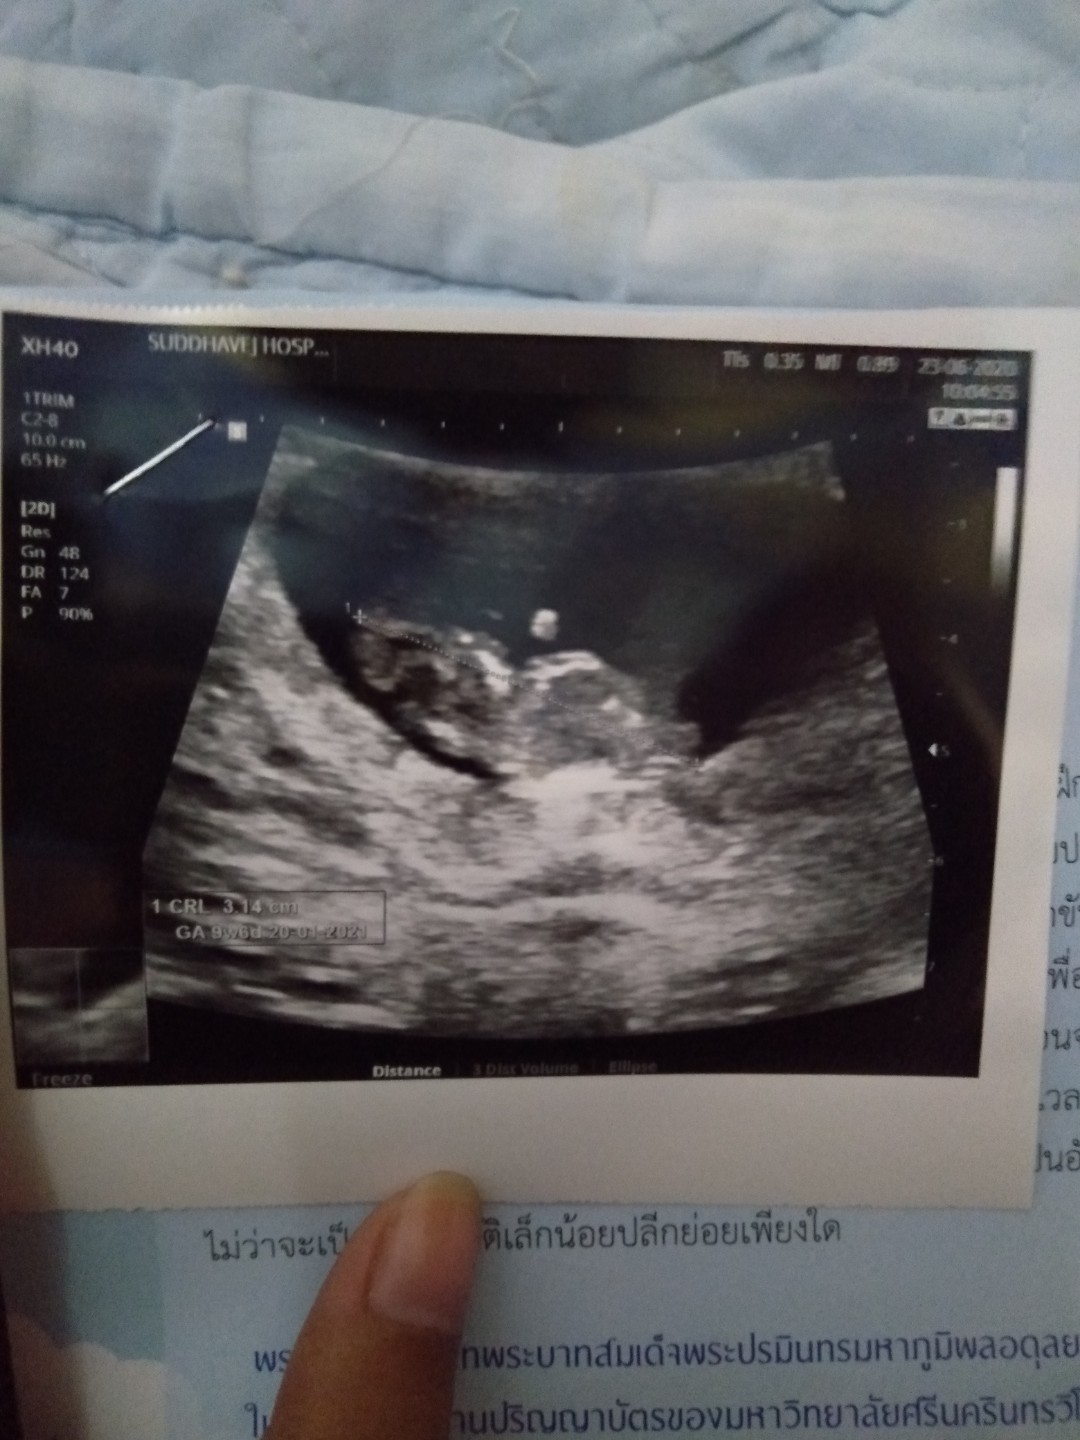

11 สัปดาห์ ซาวด์มาเจอลูกแบบนี้ถือว่าเขาตัวใหญ่ไหมคะหรือปกติ

ปกติจ้า นี้ตอน9สัปดาห์